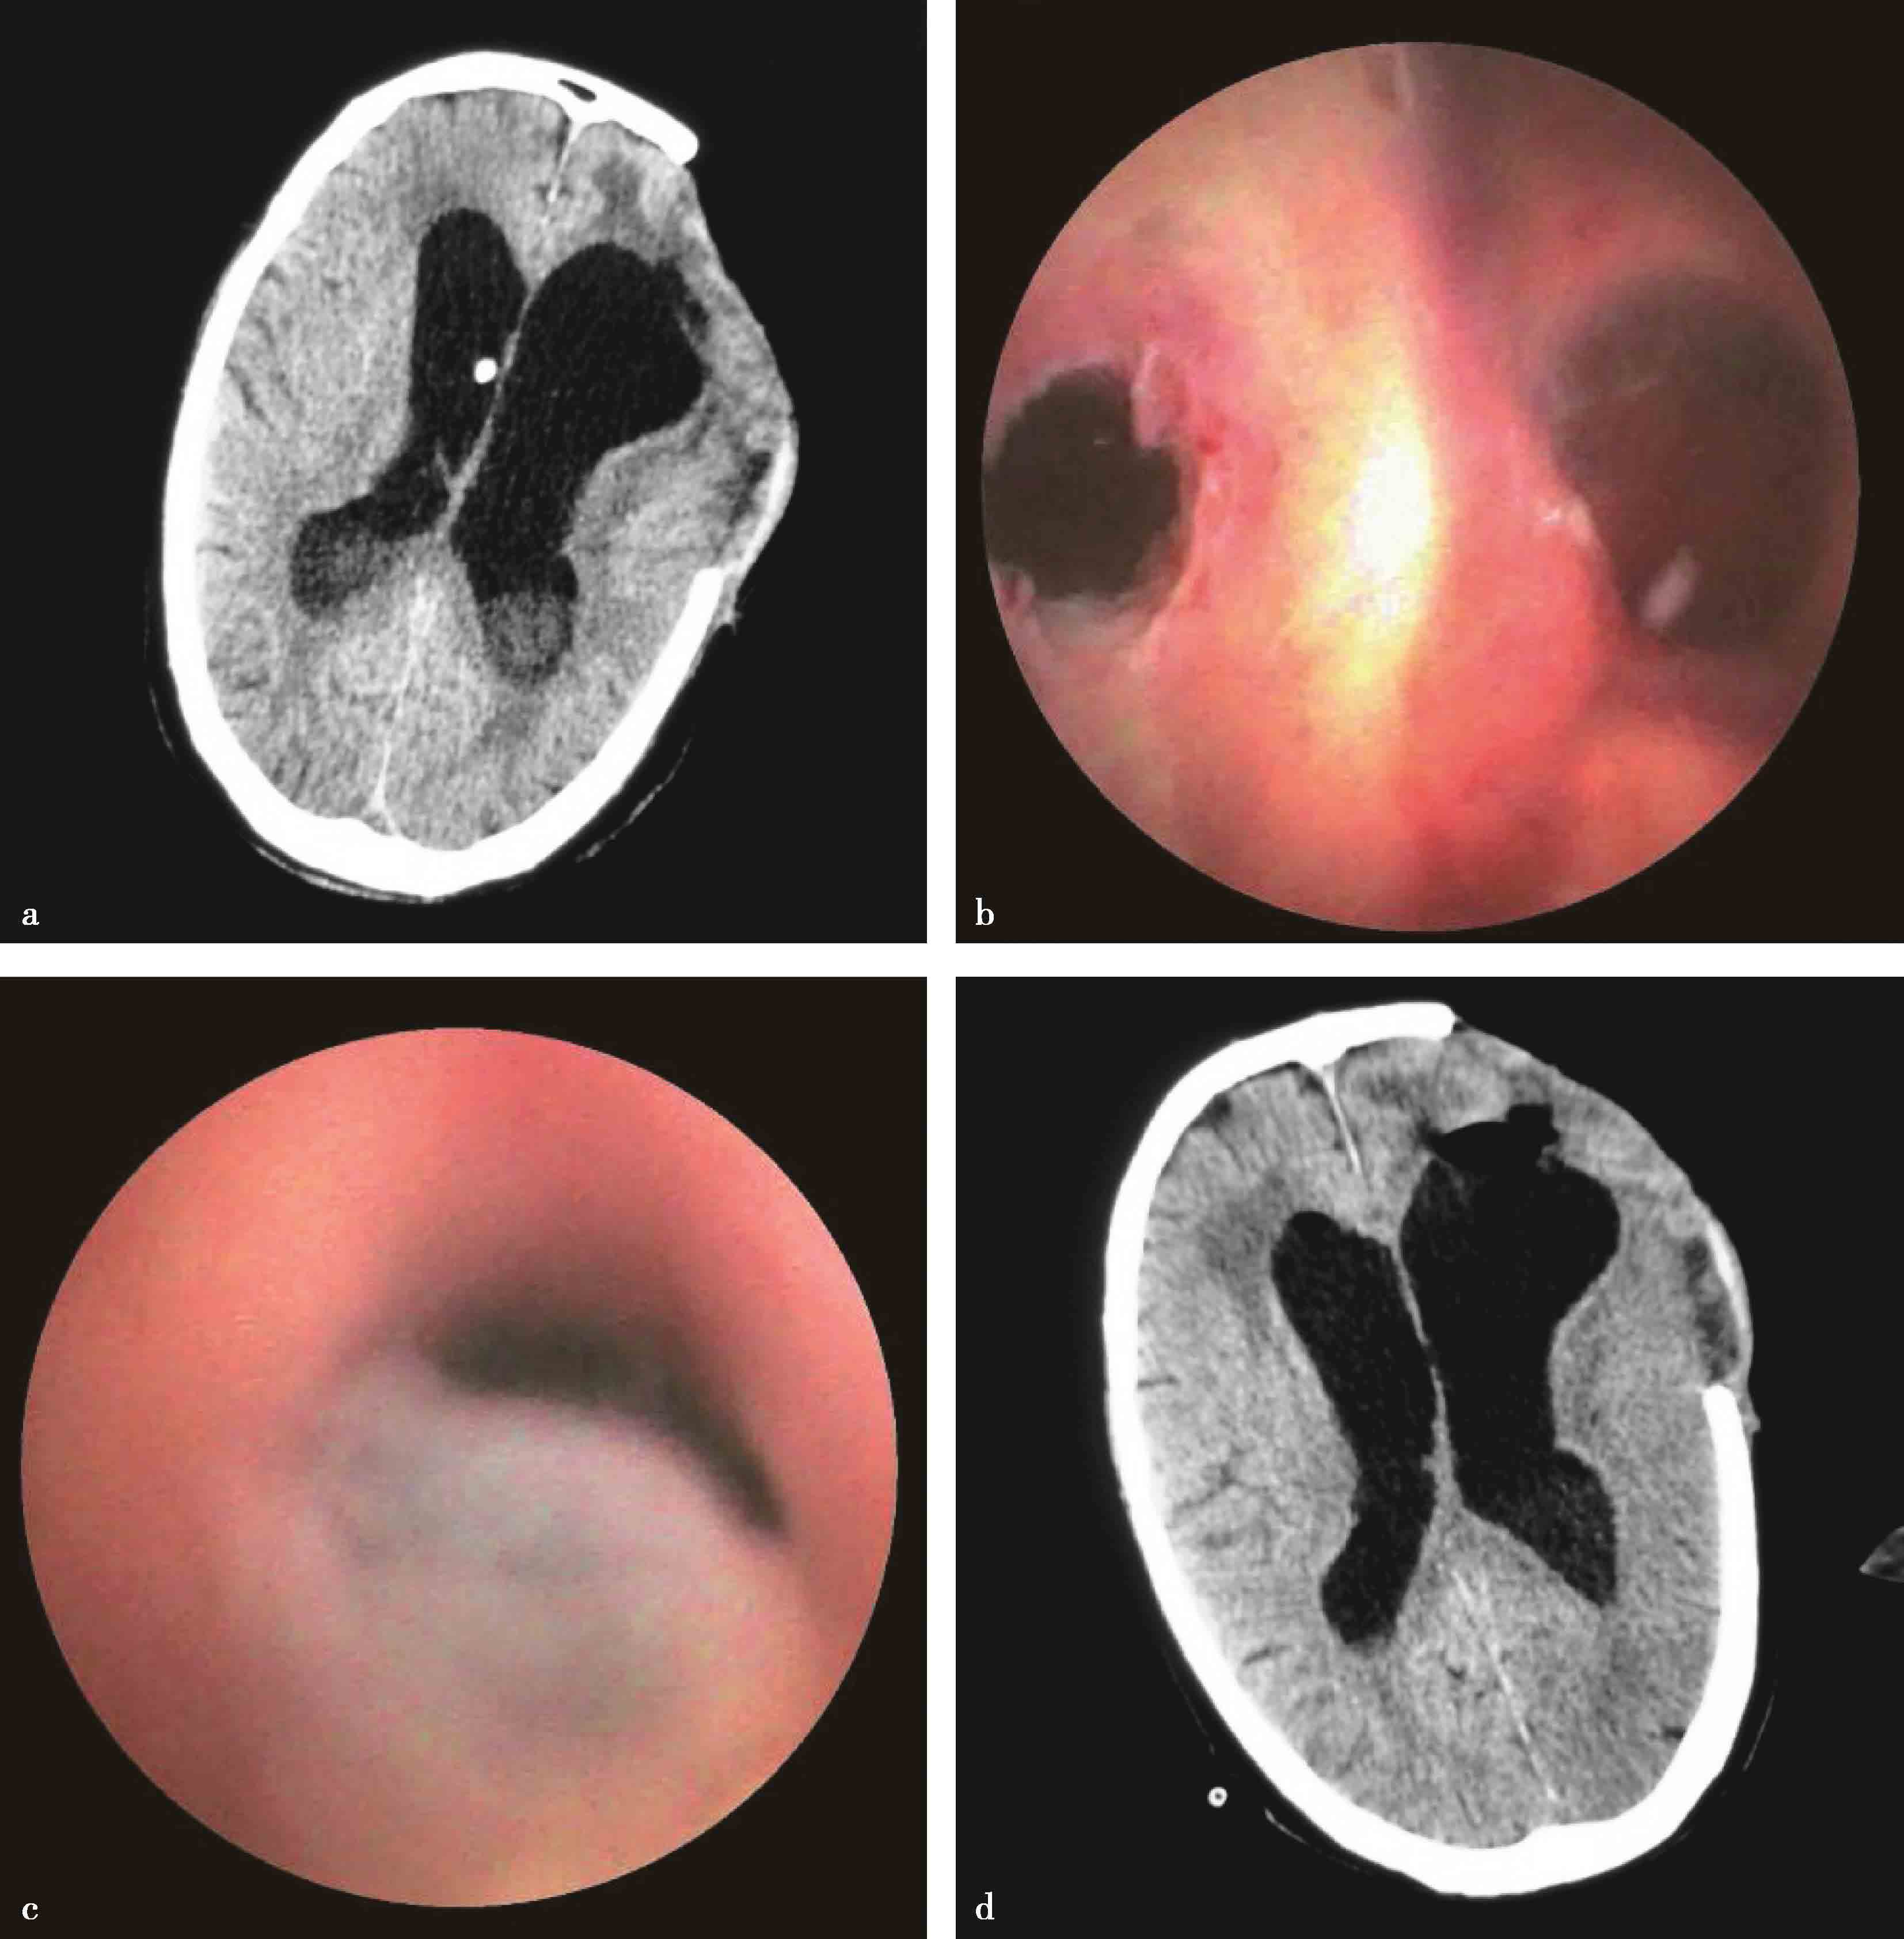

术后感染是脑脊液分流手术严重并发症之一,脑室端感染引起脑室炎,腹腔段感染导致腹膜炎,腹腔包裹或腹腔积液。分流感染一旦确诊,需尽早取出分流管,感染控制后再行后续治疗。内镜下脑室灌洗清除脑室内积脓,对脑室系统进行一次彻底清创,借助腹腔镜对腹腔感染进行探查、灌洗引流,可明显缩短分流术后感染的治疗过程(图3-1-4-8)。

图3-1-4-8 脑室积脓的内镜治疗

a.头颅CT检查显示分流术后脑室积脓;b.经室间孔、透明隔造瘘口清除双侧脑室及第三脑室内积脓;c.清除导水管内积脓,经导水管清除第四脑室内积脓;d.术后头颅CT示脑室内积脓减少